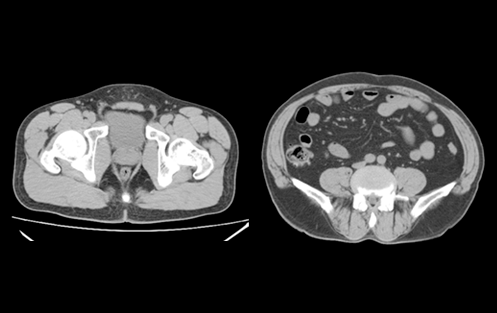

臨床圖像